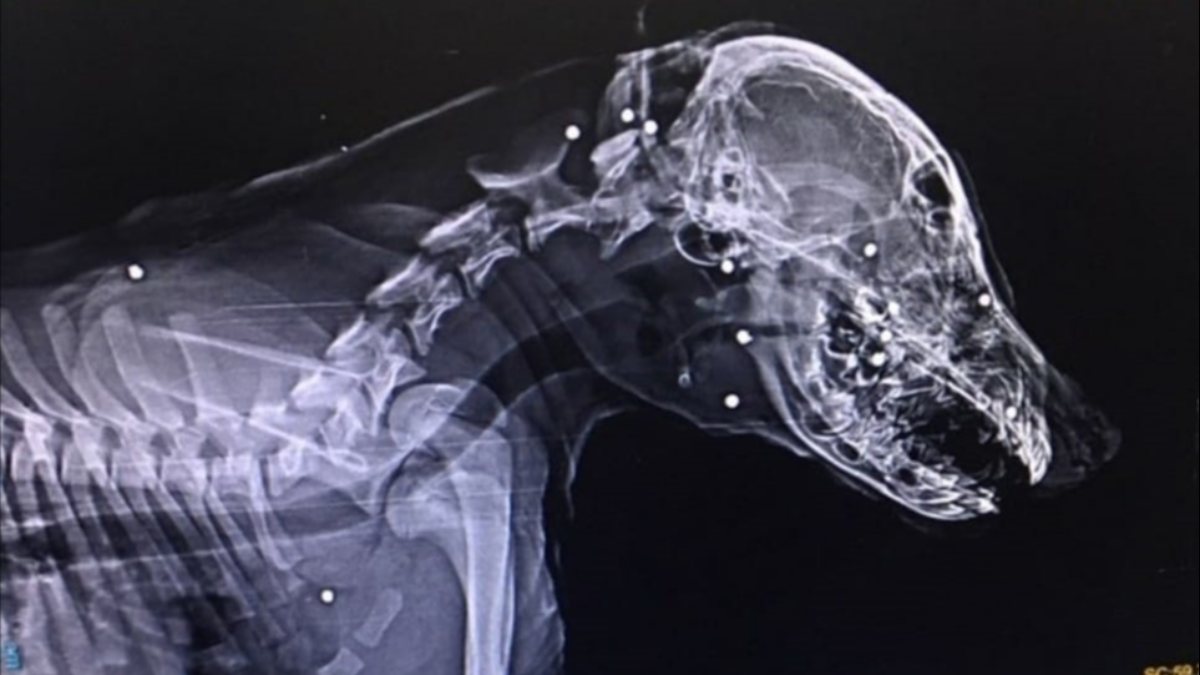

Devrek ilçesinde sahipli bir köpek, kimliği belirsiz kişilerce tüfekle suratından vurularak ağır yaralandı.

Zonguldak'ın Devrek ilçesinde Mert Ekşi’ye ait aylık sahipli köpek, kimliği belirsiz kişi veya kişilerce tüfekle suratından vurularak ağır yaralandı.

Tedavisi için köpeğini aracıyla Zonguldak'a götüren Ekşi’nin köpeğini vuran veya vuranlar için polis, geniş çağlı soruşturma başlattı.